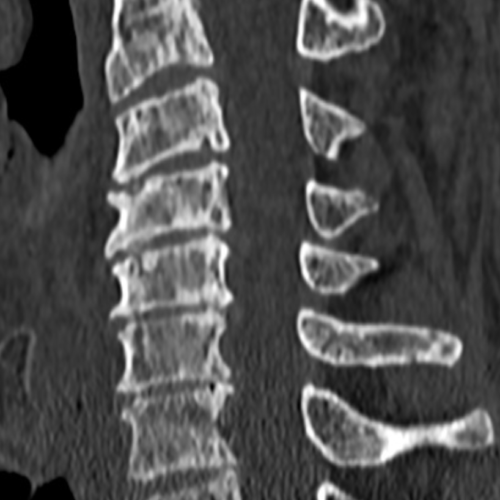

Cet examen est réalisé pour analyser le rachis cervical de C2 à T1. Il analyse les vertèbres, les disques, les nerfs, le canal cervical, les articulaires postérieures.

Cette examen ( TDM lombaire) permets de diagnostiquer:

- Les hernies discales

- Les pincements discaux

- l’arthrose zygapophysaire postérieure

- Le canal cervical étroit (rétréci)

- L’uncodiscarthrose

- Les spondylolisthésis

- Les tassements de vertèbre